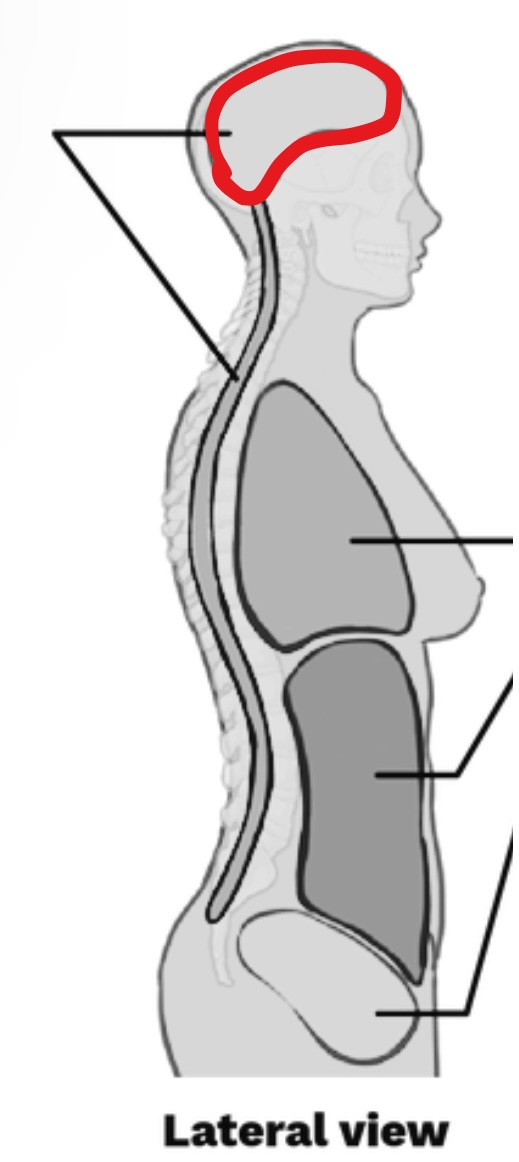

What Cavity is this?

Cranial Cavity